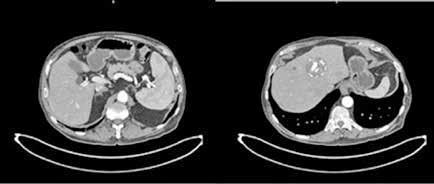

Localizada en los segmentos VII, V y parte del IV, entre las venas suprahepáticas (VSH) derecha y media, contactando con ellas en su origen. Caudalmente llega hasta la bifurcación hiliar, cercano a la bifurcación portal. Esta masa presenta una captación periférica en fase arterial y algo más isodensa en fase venosa y tardía, con un área central heterogénea e hipodensa en estas últimas fases. Con este comportamiento radiológico, se establece un diagnóstico de sospecha de hepatocarcinoma fibrolamelar o adenoma. Como variante anatómica, se objetiva una arteria hepática que nace de la arteria mesentérica superior (Figura 1). El paciente es ingresado en Digestivo para estudiar la lesión. Se realiza una Resonancia Magnética (RM) y se establece un diagnóstico de sospecha de hepatocarcinoma fibrolamelar (Figura 2). Se descartó una biopsia por el riesgo de resangrado que presentaba. La alfafeto proteína solicitada durante el ingreso fue normal. Dado que se trata de una lesión hepática sintomática y que ha presentado un sangrado, está indicada la resección de la lesión, pero su tamaño y localización lo impiden. La lesión está tan cerca de las VSH que resulta imposible disecarlas y seccionarlas con seguridad, siendo imposible la cirugía. Se comenta el caso en el comité multidisciplinar y se decide embolizar la tumoración con el objetivo de evitar un nuevo sangrado y disminuir su tamaño para separarla de las estructuras vasculares. Se cateteriza la arteria hepática, desde la mesentérica superior. Se emboliza con micropartículas

la hepática derecha y una rama más distal de la hepática izquierda, preservándose los segmentos II y III. (Figura 3)

En el TC de control la lesión ha disminuido de tamaño a 10 x 7.4cm. Se realiza además una volumetría hepática y los segmentos I-III suponen el 29 % de la masa hepática, siendo este remanente insuficiente. Con la embolización, la lesión se ha reducido de tamaño pero sigue contactando con el nacimiento de las VSH media y derecha. Su resección exige realizar una hepatectomia derecha ampliada. Precisa pasar y ligar ambas venas en su origen y sigue siendo el acceso complejo por tener delante la masa. Se sigue considerando de dudosa resecabilidad por el difícil acceso a las VSH y el riesgo hemorrágico. Se decide realizar una nueva embolización para reducir aún más el tamaño tumoral, esta vez con radioesferas de Y90. Esta segunda embolización es más selectiva y con poca afectación del parénquima sano.

Tres meses después se realiza un nuevo TC de control, que muestra la lesión en el mismo lugar, actualmente de 7,4x5,9 cm de diámetros (previo de 9,8x7,5 cm). En la actualidad se ha alejado de las VSH, pero contacta y desplaza la vena porta derecha y la arteria hepática. Además se visualiza una leve dilatación de la vía biliar intrahepática izquierda, de nueva aparición. Se presenta en comité una vez más y se decide colocar un drenaje biliar interno-externo, dado la dilatación de vía biliar que presenta el paciente. Además se realiza una embolización portal derecha, para así aumentar el remanente del hígado izquierdo que era del 29%. Se realiza una nueva volumetría hepática tras la embolización portal y se comprueba que el futuro remanente hepático había aumentado al 42%.

Resumiendo: Teníamos una masa hepática inicialmente irresecable que se ha tratado con dos embolizaciones arteriales, consiguiendo una disminución del tamaño y una mayor separación de las venas suprahepáticas. Sin embargo, se ha acercado a la bifurcación portal y comprime la vía biliar (dilata la vía intrahepática izquierda asociando una elevación de bilirrubina). Se ha colocado un drenaje biliar interno-externo. Se ha embolizado la porta derecha, consiguiendo pasar de un volumen de remante hepático del 29% al 42%, siendo ahora posible su resección. El acceso a las VSH sigue siendo complejo y arriesgado, pero menos que al inicio (Figura 4).

Figura 2 (A y B).

RM: Gran masa hepática localizada en segmentos VII, V y parte del IV. Comportamiento radiológico característico de hepatocarcinoma.

A) T1, imagen hipointensa entre VSH derecha y media.

B) T2, lesión hiperintensa con centro hipointenso.

Figura 3.

Angiografía previa a la embolización con micropartículas. A través de la femoral, accedemos a la aorta (Ao). De la aorta accedemos a la arteria mesentérica superior (AMS), de donde sale en este caso la arteria hepática (AH). Se divide en arteria hepática derecha (AHD) y arteria hepática izquierda (AHI). Se emboliza la AHD y una rama distal de la AHI. Vemos cómo ambas ramas dan abundantes ramas que irrigan la lesión.

Figura 4.

TC realizado tras las dos embolizaciones arteriales. Vemos cómo la lesión ha disminuido considerablemente de tamaño y ahora está más alejada de las VSH y de la cava. Esto permite la ligadura de las VSH en su confluencia con la cava. Inicialmente no habría sido posible por su cercanía y tamaño.